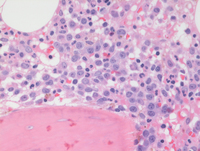

Bone marrow biopsy findings-higher power

Bone marrow biopsy at higher power demonstrates the mononuclear cells with evidence of dispersed chromatin compatible with blasts in the first two images. Paratrabecular clusters of blastic cells around the bone are also noted. The last image demonstrates a single dysplastic hypolobated megakaryocytes in the center of the field.